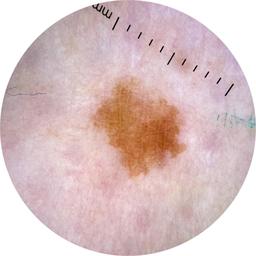

Field Value

acquisition_day 470

age_approx 65

anatom_site_1 Lower extremity

anatom_site_general lower extremity

concomitant_biopsy False

diagnosis_1 Benign

diagnosis_confirm_type single image expert consensus

family_hx_mm False

image_manipulation instrument only

image_type dermoscopic

lesion_id IL_4840301

patient_id IP_9275886

personal_hx_mm True

sex female